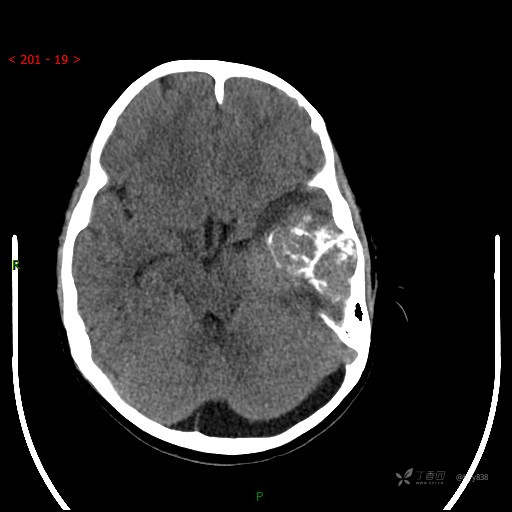

“典藏”病例分享。10岁儿童,头痛头晕一周余,CT、MRI 都有---结果公布~

简要病史:患者于一周前无明显诱因开始出现头痛头晕,无恶心呕吐,无肢体抽搐,无寒颤高热,无腹胀腹泻,无视力下降及视野缺损,上述症状休息后可稍缓解,未引起重视。 2天前患者头痛头晕不适加重,伴有恶心感,无呕吐,遂到当地人民医院行头颅CT检查示:左侧颞部占位性病变,今日家属为求进一步治疗,来我院门诊求治。门诊拟“左侧颞部占位性病变”收入我科。 患病以来,患者精神、饮食、睡眠尚欠佳,大小便如常,体力体重无明显变化。

临床诊断:左侧颞部占位

颅脑CT扫描